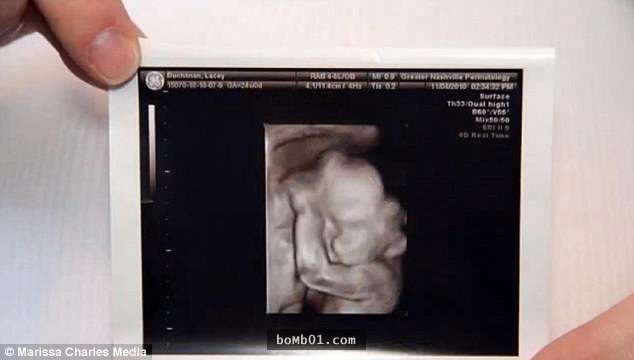

▼Lacey Buchanan是法學院的學生,她15歲時與丈夫Chris Buchanan相遇,兩人21歲步入婚姻殿堂。兩年後她懷上了寶寶,但產檢時的結果卻讓人心碎。

▼醫生告訴他們,這個孩子有羊水帶症候群。這種情況非常罕見,孕婦羊膜破裂的話,破裂處會產生一條帶狀組織,不管它卡在寶寶的哪個部位,都會造成嚴重的影響。Lacey的寶寶面部被破壞,出生後可能失明。

▼Lacey與Chris心急如焚,最終還是決定將孩子生出來。Christian的情況比他們想像中嚴重得多,他罹患層齶裂,沒有上顎,嘴巴無法閉合,還沒有雙眼。出生後的前幾天,他是在新生兒加護病房度過的。